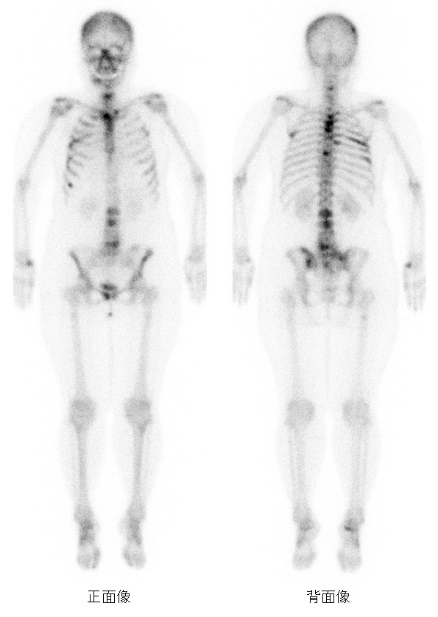

RI検査(Radio Isotope(ラジオアイソトープ))は核医学検査やアイソトープ検査とも呼ばれています。微量の放射線を出す医薬品(放射性医薬品)を体内に投与(注射・吸入等)して、臓器や病変に取り込まれた放射性医薬品から放出される放射線を特殊なカメラで画像化する検査です。

検査で用いられる放射性医薬品による被ばくは人体に害を及ぼす量ではありません。また、薬による大きな副作用もほぼありません。安心して検査を受けていただけます。

撮影に要する時間は30分から75分程度と長めですが、痛みを伴うことはほとんどありません。

装置は2検出器型のSPECT-CT装置です。

寝台が動くことで全身の撮影ができます。

また、カメラが回転することで輪切り(断層画像)の画像の撮影も可能です。

骨シンチグラフィ(「こつシンチ」と呼ばれています。)、脳血流シンチグラフィ、心筋血流シンチグラフィ、心筋MIBGシンチグラフィ、ダットスキャン、レノグラム、RI内用療法(ゾーフィゴ静注)etc…

全身の検査です。

骨の代謝や反応が盛んなところに集積するので、骨の腫瘍や骨の炎症、骨折の診断などの目的で行われる検査です。